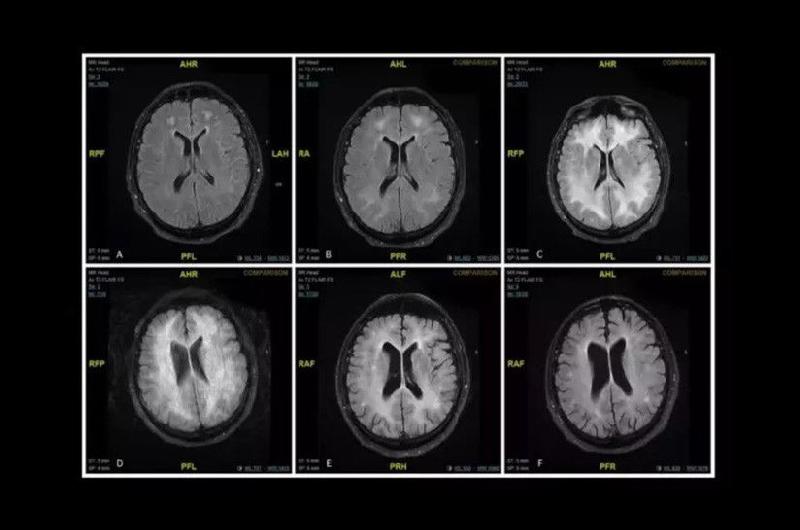

Revelan Imágenes De Cómo La Cocaína Come El Cerebro De Un Adicto La cocaína es una droga que ha causado preocupación a nivel mundial debido a su impacto en la salud de quienes la consumen. ¿sabías que tiene efectos devastadores en el cerebro? en este artículo, te explicaremos cómo la cocaína afecta al cerebro y cuáles son sus consecuencias a corto y largo plazo. El consumo de drogas trae consecuencias extremadamente negativas para todo el organismo, pero especialmente para el más importante, que es el cerebro. este y el corazón son los primeros órganos.

Impactante Así Devora El Cerebro La Cocaína Consumida Una Resonancia

Cocaína Así Devora El Cerebro Su Consumo